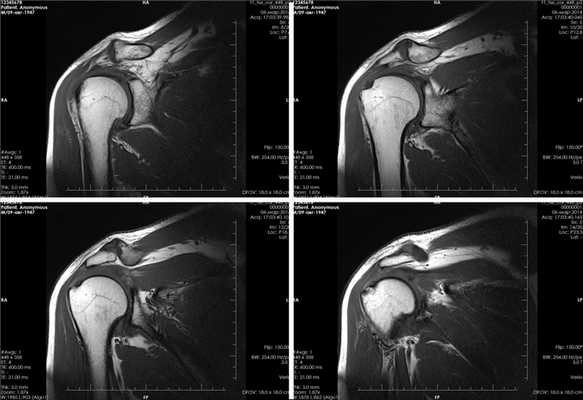

(Справа) На передне-задней рентгенограмме определяется латеральное направление типичного вывиха. Видна вывихнутая головка лучевой кости с большим дефектом, вывихнутая локтевая костью и отломок перелома головки лучевой кости. Примерно 90% вывихов предплечья являются заднебоковыми по направлению. (Слева) На боковой рентгенограмме у подростка 11 лет определяется задний вывих локтевого и лучеголовчатого суставов. Отломки находятся в суставе.

(Справа) На передне-задней рентгенограмме у этого же пациента можно видеть медиальное смещение лучевой и локтевой костей. Примерно 90% вывихов локтевого сустава являются заднебоковыми. Видимые в боковой проекции отломки исходят из головки мыщелка плечевой кости и головки лучевой кости. (Слева) В передне-задней проекции локтевого сустава после попытки закрытого вправления заднебокового вывиха предплечья видны отломки головки лучевой кости и венечного отростка.

(Справа) На боковой проекции у этого же пациента определяется задний вывих лучеголовчатого сустава с множеством костным отломков в суставе и дефект в головке лучевой кости. Локтевой сустав неконгруэнтный, что указывает на неполное вправление.

3. КТ при вывихе предплечья:

• После вправления:

о Ищут ущемленные костные отломки и донорские участки

о Маленькие костные отломки лучше видны на КТ, чем на МРТ

4. МРТ при вывихе предплечья:

• Информативна для характеристики сопутствующего повреждения связок:

о Латеральная локтевая коллатеральная связка

о Лучевая коллатеральная связка

о Локтевая коллатеральная связка

• Помогает выявить костно-хрящевые дефекты:

о Чаще встречаются в случае отсроченного вправления